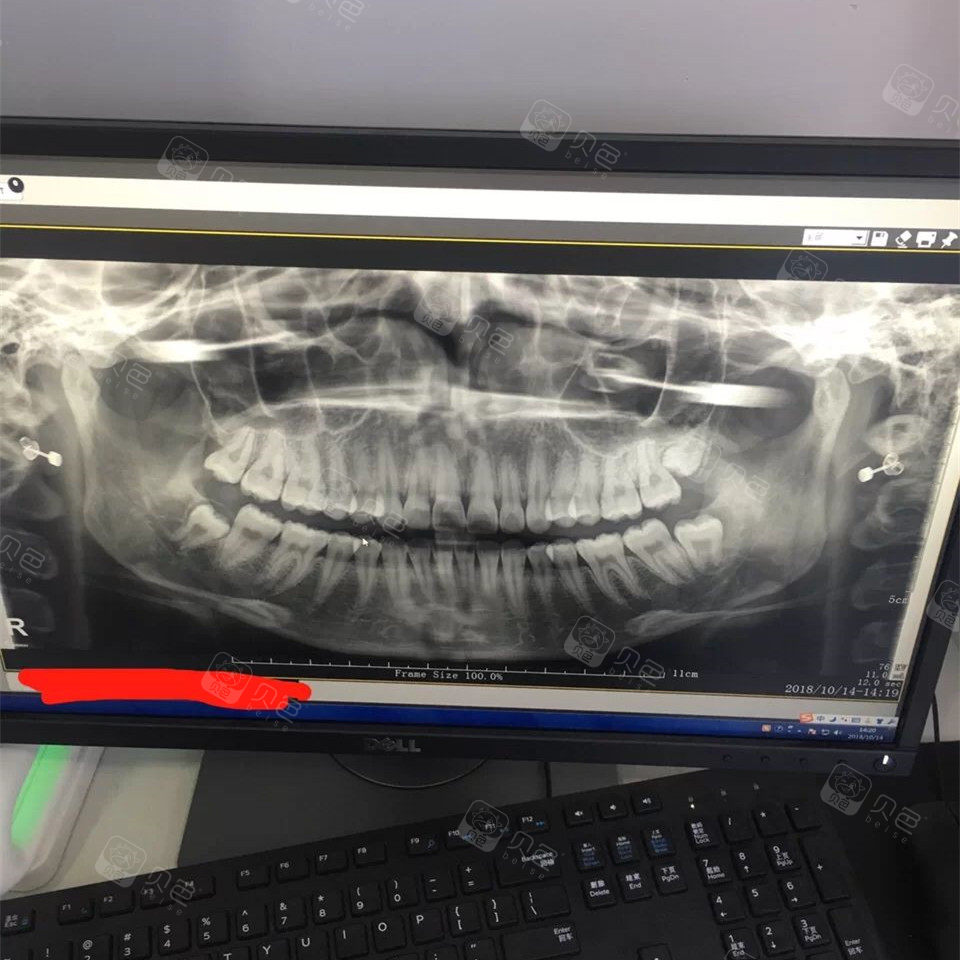

根管治疗前拍的一个牙片.想询问一下,左下的小矮牙是智齿吗?

去年治牙拍的牙片,大家看我有智齿吗?

牙片是去年国庆节拍的 当时因为还在根管所以拔牙的计划暂时搁浅